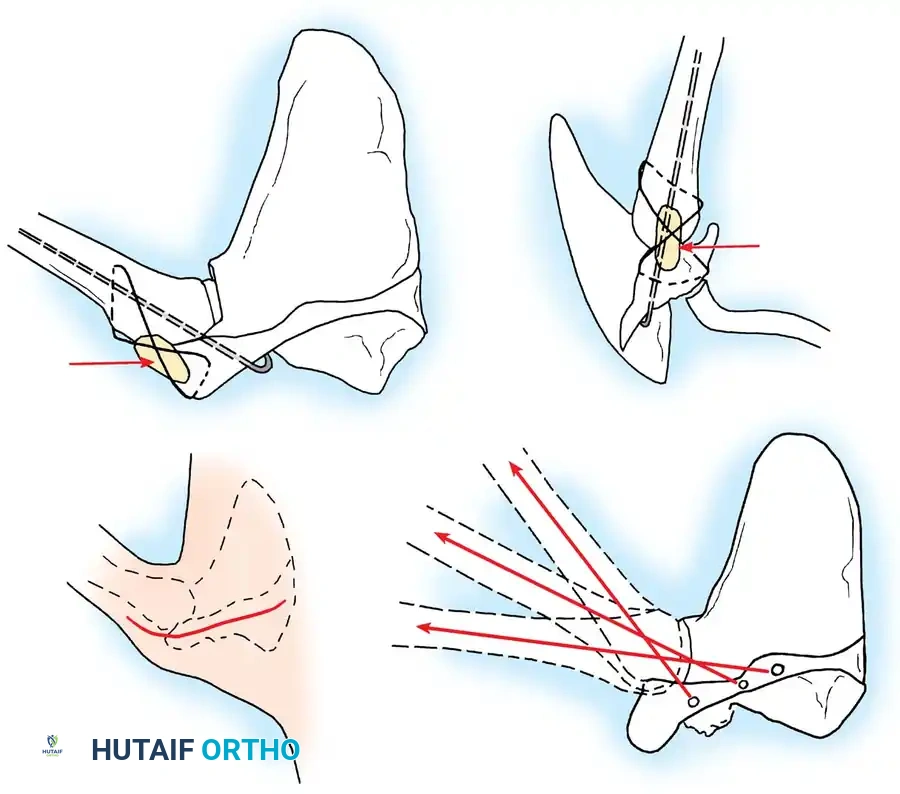

3. Joint Preparation and Decortication

Meticulous preparation of the bony surfaces is paramount to achieving a solid arthrodesis. All articular cartilage must be aggressively removed using a combination of osteotomes, gouges, and high-speed burrs.

The glenoid is decorticated down to bleeding subchondral bone. The humeral head is similarly denuded. To maximize the surface area for fusion, the undersurface of the acromion is decorticated, and a corresponding flat surface is created on the superior aspect of the greater tuberosity.

In some techniques, an intra-articular osteotomy of the humeral head is performed to create a flat, broad cancellous surface that perfectly mates with the decorticated glenoid.

4. Provisional Fixation and Positioning

The arm is placed into the predetermined optimal position (20-30° abduction, 20-30° flexion, 40° internal rotation). The hand-to-mouth test is performed. Once the position is confirmed, heavy Steinmann pins or K-wires are driven from the lateral humerus, through the humeral head, and into the glenoid vault to provisionally hold the construct.